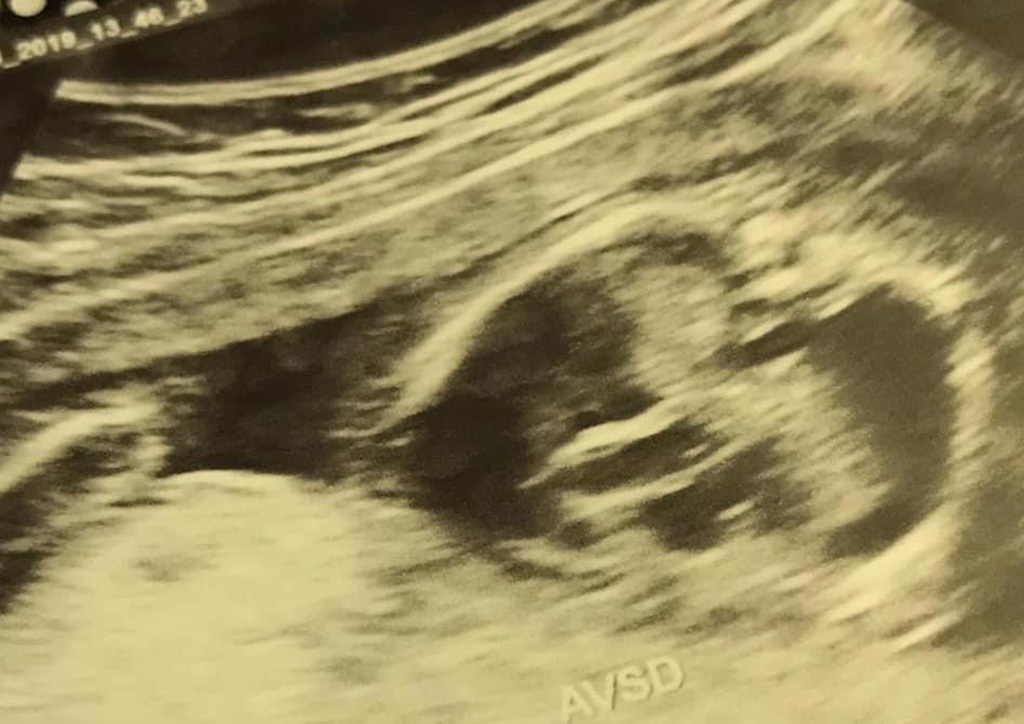

“Your baby has pleural effusion, there is water in his lungs, he also has a congenital heart disease called AVSD, it’s Atrioventricular Septal Defect which basically means he has a big hole in the middle of his heart”.

She then showed me the screen but all I saw was a blurry sea of black and white. She proceeded in telling me that she also found several more defects. Around this time, I was already in tears but I was trying hard to listen to what she was telling me so I could remember everything when I had to tell my husband.